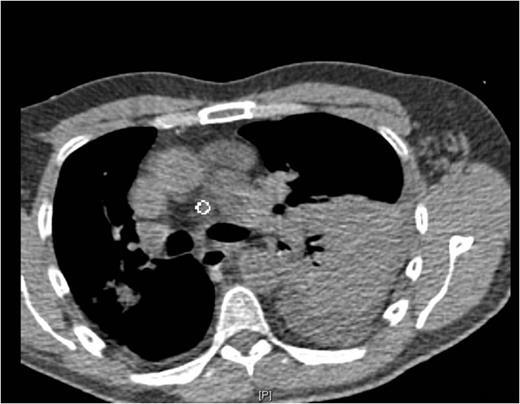

Chest pain persisted and the patient required higher pressure CPAP to maintain adequate oxygenation. Auscultation consistently showed decreased air-entry in the lung bases. On day 3, a repeat chest x-ray showed a left lower lobe collapse above the gastric bubble in the mid zone of the chest (Fig. 4 & 5). CTPA done on the same day to exclude pulmonary embolism confirmed a para-oesophageal hernia that was pushing against the left lung base. Ultrasound scan of the left chest also showed movement of the diaphragm below the gastric bubble.

Post-op CT-scan demonstrating the left sided pleural effusion with collapse /consolidation & patchy opacification on the right side.